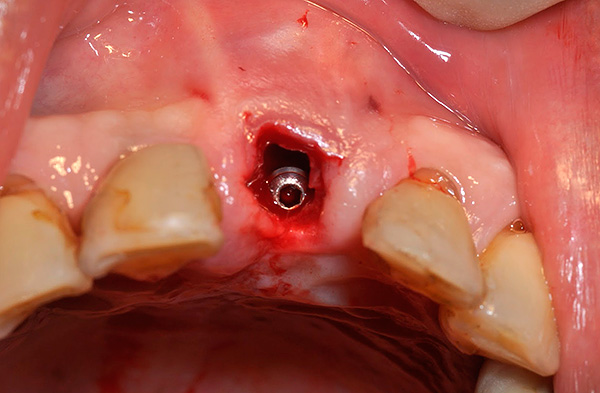

Talvez também seja importante mencionar a divergência de suturas, frequentemente aplicada à ferida após o implante. A foto abaixo mostra um exemplo do estado normal das suturas imediatamente após a cirurgia:

A divergência das suturas, como complicação, quase nunca é sinal de implantes dentários mal sucedidos, pois caracterizam mais o resultado do comportamento da própria pessoa. As violações podem ser muito diferentes: desde a não observância dos princípios de higiene bucal e ignorando as recomendações do médico, até o "toque" não autorizado na cavidade oral com dedos, palitos de dente, etc., o que leva a danos mecânicos nas suturas ou contribui para o início do processo inflamatório. Isso provoca a divergência de costuras no futuro.